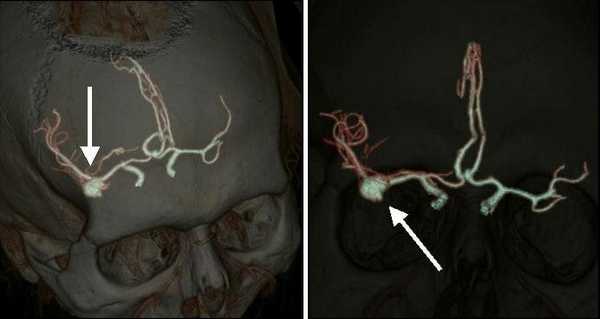

Если после проведения МРТ или КТ у врача остаются сомнения в диагнозе, если у данной аневризмы достаточно сложная форма либо очень небольшие размеры, большим подспорьем может стать дигитальная субтракционная ангиография (ДСА). Дигитальная - значит «цифровая». Субтракционная означает, что при исследовании исключаются изображения скелета, мягких тканей, видны только сосуды. Причём современная методика позволяет получать изображение в формате 2D (двухмерном) и 3D (трёхмерном) и даже вращать картинку, что даёт возможность уточнить локализацию аневризмы и оценить её расположение по отношению к магистральным сосудам головного мозга. Это помогает доктору понять, нужна ли операция в данном случае, и если да, то выбрать вид оперативного вмешательства и доступ к аневризме. Позже ДСА позволяет наблюдать за аневризмой (в том числе и после операции).

- Ангиографию. Церебральная ангиография позволяет установить расположение, форму и размеры аневризмы. В отличие от рентгенологической ангиографии магнитно-резонансная (МРА) не требует введения контрастных веществ и может проводиться даже в остром периоде разрыва аневризмы сосудов головного мозга. Она дает двухмерное изображение поперечного сечения сосудов или их объемное трехмерное изображение.

КТ-ангиография головного мозга (3D-реконструкция). Аневризматическое расширение левой средней мозговой артерии